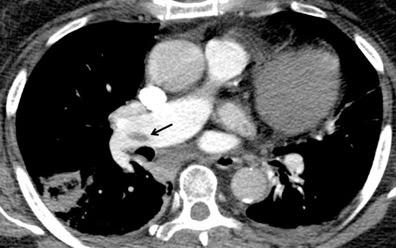

25. ELEVACIÓN UNILATERAL. TEP

Tromboembolismo pulmonar Diafragma elevado 20%